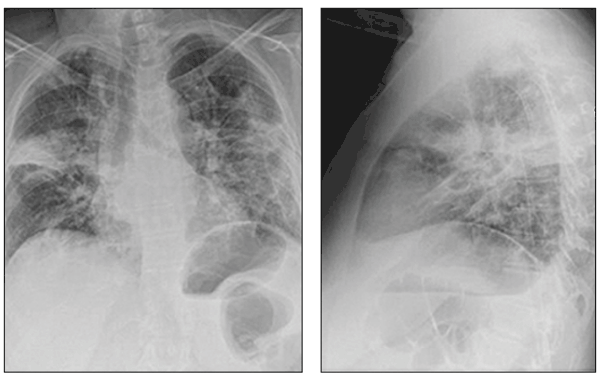

Multifocal airspace opacities can be seen on these chest radiographs from a patient with drug-induced organizing pneumonia, a unique form of lung disease.

Chest radiographs demonstrate patchy areas of consolidation, ground-glass and nodular opacities, and bronchial wall thickening and dilation.